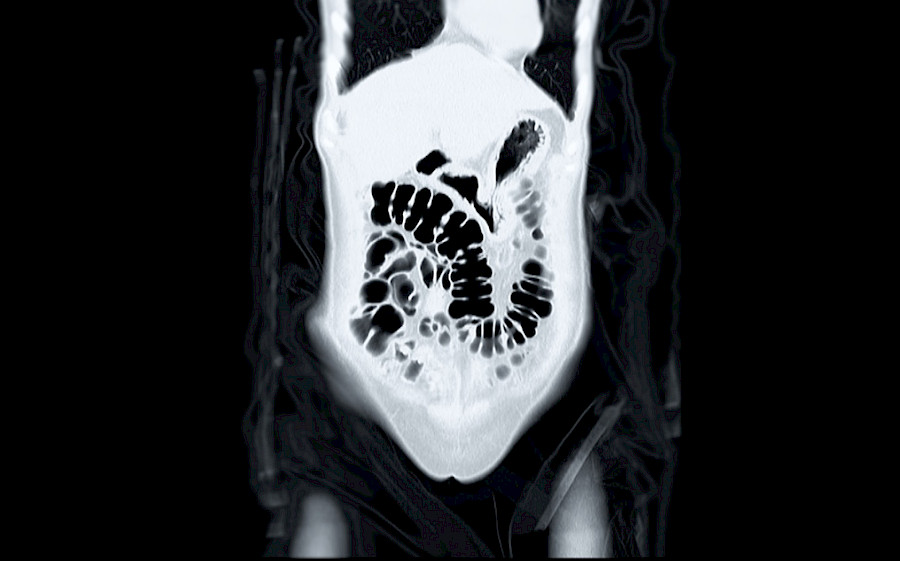

CT kolonoszkópia: a legfontosabb tudnivalók

CT kolonoszkópia: a legfontosabb tudnivalók ... A CT kolonoszkópia egy korszerű módszer a vastagbél vizsgálatára. Mit jelent a CT kolonoszkópia és…